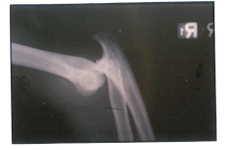

E.G. is a young man who was lending a helping hand in his father’s auto shop when he nearly gave up that hand to a freak accident. He was changing a truck tire when it suddenly exploded causing his elbow to dislocate and nearly amputate his hand.

The wrist injury was so severe that it required a surgical fusion once he had been transferred to a Miami Hospital from a more remote location.

The hand surgeon on call had not accepted the transfer due to the severity of the injury, but Dr. Badia was later called and authorized the transfer so that he could perform the reconstruction.

E.G. was an inspiration to the other patients in therapy undergoing months of rehabilitation so that he could regain nearly normal motion in his elbow and a functioning hand seen in the comparison photos to his opposite, normal hand